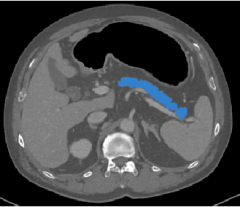

NVFlare and its predecessors have been used in several real-world studies exploring FL for healthcare scenarios. The collaborations between multinational institutions tested and validated the utility of federated learning, pushing the envelope for training robust, generalizable AI models. These initiatives included FL for breast mammography classification [32], prostate segmentation [33], pancreas segmentation [37], and most recently, chest X-ray (CXR) and electronic health record (EHR) analysis to predict the oxygen requirement for patients arriving in the emergency department with symptoms of COVID-19 [6].